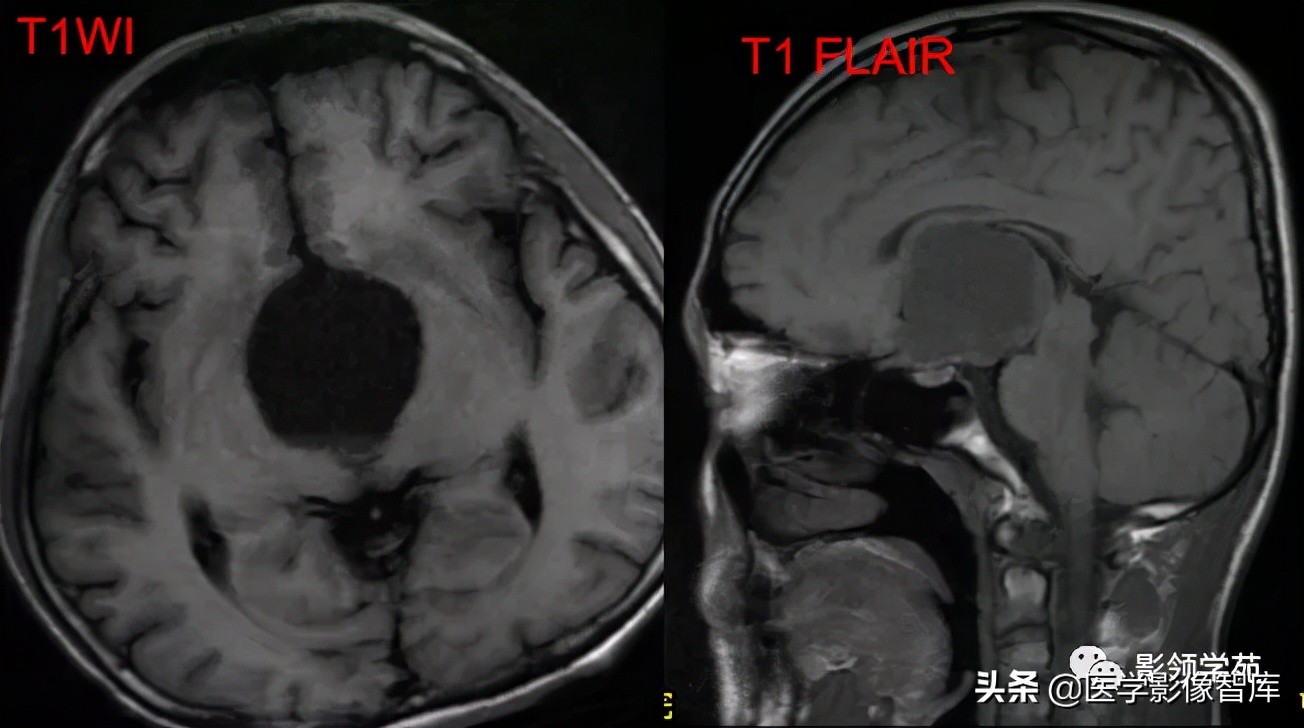

女 72岁,发现糖尿病3年余

鞍上区见一团块状稍高密度影,边界尚清,密度均匀。

鞍上右上方见一类椭圆形流空影。

病灶明显强化(瘤内血栓未强化),边界清楚,与右侧颈内动脉海绵段分界不清。垂体大小、形态未见异常。